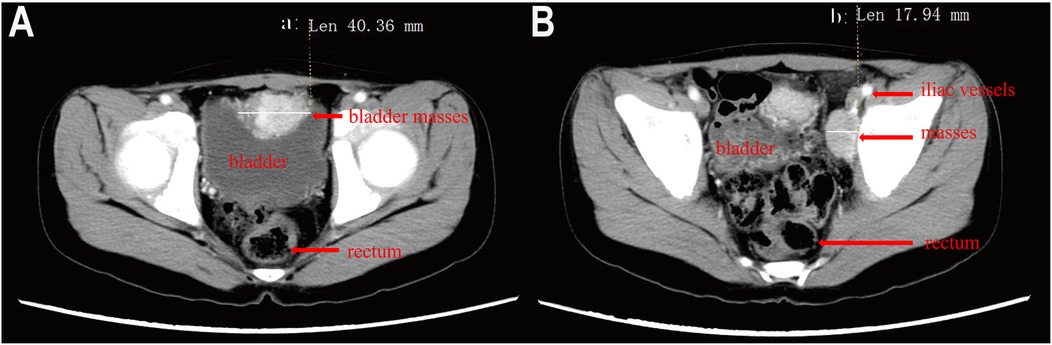

As previously reported, Case 2 had a complex clinical presentation. Comprehensive clinical details of this patient were provided in our previously published article in Frontiers in Pediatrics (9). The child presented with bilateral adrenal masses, with the left tumor measuring approximately 40 mm and the right tumor 12 mm in diameter (Figure 2A). Pheochromocytoma was diagnosed based on the patient's medical history, blood tests, and imaging studies. Initial treatment involved beta-blockers, phentolamine, and phenoxybenzamine to control blood pressure. During the perioperative period, the patient developed multiple complications, including fever, diarrhea, pulmonary infiltrates, and hepatic dysfunction characterized by elevated transaminases (ALT 134 U/L, AST 233 U/L), hypoalbuminemia (22 g/L), and electrolyte imbalances (Na+ 129 mmol/L, K+ 3.2 mmol/L, Cl− 90 mmol/L, Mg2+ 0.57 mmol/L). Coagulation abnormalities were noted, with a prolonged PT (25.8 s) and aPTT (45.7 s). The patient subsequently developed polyuria and left femoral vein thrombosis, with worsening electrolyte disturbances secondary to persistent polyuria. An emergency resection of the right adrenal tumor was performed, which was confirmed as pheochromocytoma by pathological examination. During perioperative management, the patient developed diabetes insipidus, evidenced by low urine osmotic pressure and low blood osmotic pressure, with brain and pituitary MRIs showing no abnormalities. Multidisciplinary consultation led to addressing the metabolic disruption may cause by adrenal gland space occupation. Despite mineralocorticoid supplementation, the patient's condition worsened, prompting emergency resection of the adrenal tumor. The operation was performed with colloids and crystalloid fluids, and no further episodes of diabetes insipidus occurred. Oral mineralocorticoid therapy was continued for three months postoperatively. Three years later, follow-up imaging revealed enlargement of the left adrenal tumor (Figure 2B). Genetic testing identified a heterozygous mutation in the VHL gene, confirming a diagnosis of Von Hippel-Lindau (VHL) syndrome. To achieve adequate blood pressure control, the patient received a combination of phenoxybenzamine (initiated at 10 mg and titrated to 20 mg every 12 h), amlodipine (5 mg once daily), and metoprolol (25 mg once daily). In addition, dietary sodium intake was increased over approximately three weeks to facilitate plasma volume expansion. The left adrenal tumor was resected laparoscopically. One year post-surgery, the patient's blood pressure had returned to near-normal levels.

Figure 2. Contrast-enhanced CT image of a child with pheochromocytoma. (A) bilateral adrenal masses, with the left 40 mm and the right 12 mm at the first hospitalization, (B) The left adrenal mass measures 39 mm in diameter).